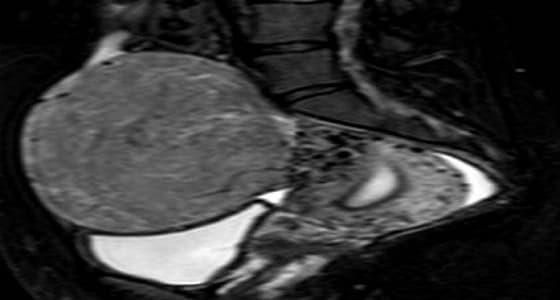

تم عمل أشعه موجات فوق صوتية ورنين مغناطيسي على الحوض وإتضح أن السيدة لديها ورم ليفي كبير جدا يضغط على الرحم ويتسبب في الإجهاض المتكرر ويحتوي على أوعيه دموية كثيرة وغزيرة.

تم حقن الأوعية الدموية المغذية للورم وسدها بالكامل و بذلك تم الحفاظ علي رحمها وأصبحت لا تعاني من اي الالم وإحياء أملها في الإنجاب بعد فضل من الله.